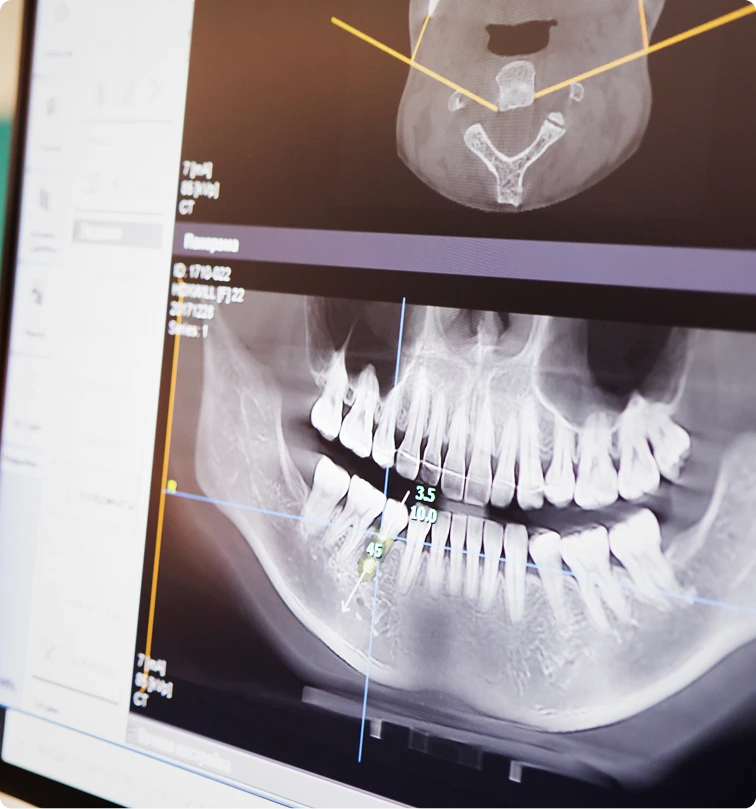

Facial analysis

Photographs and

structural evaluation to

plan proportions and

technique.